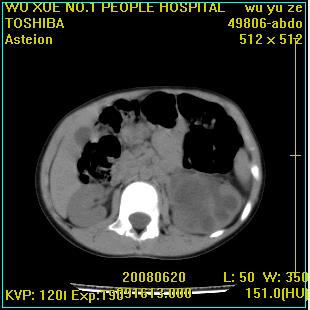

标题: PED0851:患儿,7岁,左腰部外伤一天,伴大量肉眼血尿。 [打印本页]

标题: PED0851:患儿,7岁,左腰部外伤一天,伴大量肉眼血尿。

左甚积液,输尿管近端扩张,考虑输尿管中下段梗阻

左输尿管上段梗阻伴左肾盂肾盏扩张积液

左肾积液,输尿管近端扩张,考虑输尿管中下段梗阻  ,左肾结核?

1 肾盂输尿管交界处狭窄

2 囊性肾发育不全

左肾积液,上段输尿管扩张。

左侧输尿管中段狭窄伴输尿管肾积水,考虑先天性狭窄可能性大.

左肾重度积水,原因不明;不排除左输尿管上段迷走血压迫或先天性狭窄所致可能。

左肾积水,输尿管上段扩张.考虑左输尿管下段狭窄受阻.

左肾积水,左侧输尿管上段扩张。

支持左肾积水,输尿管上段扩张.考虑左输尿管下段狭窄受阻

左肾重度积水

支持左肾积水,输尿管上段扩张.考虑左输尿管下段狭窄受阻。